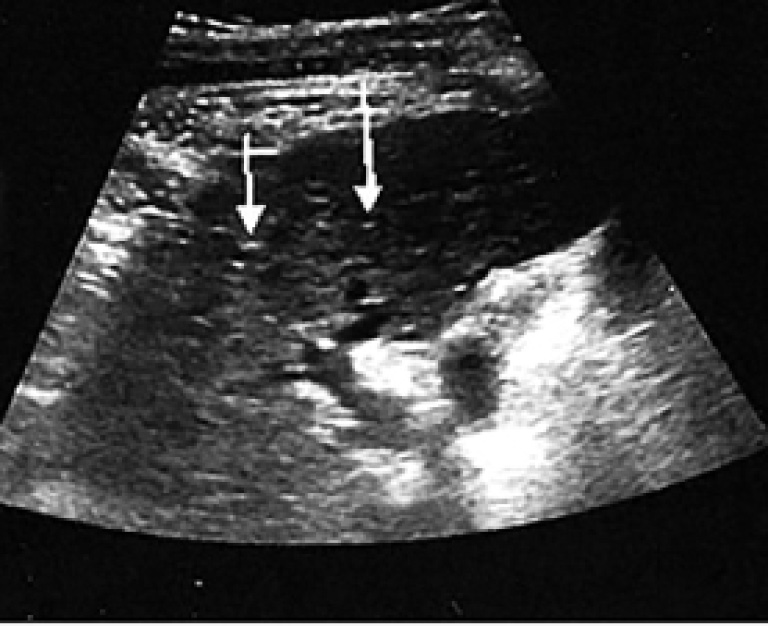

С целью дальнейшей визуализации вводимых клеточных структур в организме пациента предварительно культура аутологичных МСК была обработана наночастицами оксида железа. Через сутки после проведения клеточной терапии пациенту были выполнены МРТ органов брюшной полости и грудной клетки и УЗИ печени (рис. 2, 3).

Рис. 3. УЗИ печени через 1 сутки после введения аутологичных МСК в артериальное русло печени. Стрелкой указаны области печени, в которых визуализируются маркированные стволовые клетки

На представленном снимке МРТ органов брюшной полости введенные стволовые клетки визуализируются в правой доле печени. При этом в каких-либо других органах брюшной полости, а также в грудной клетке клеточные структуры не выявлены. При УЗИ печени также удалось визуализировать фиксированные в правой доле меченые клеточные структуры, однако по сравнению с МРТ не представлялось возможным четко определить границы располагающихся МСК.